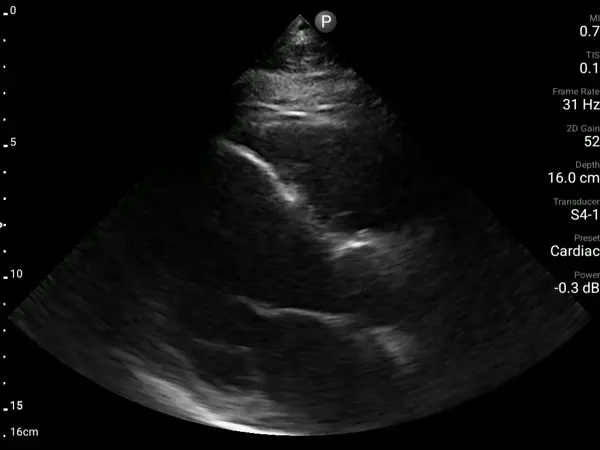

A 95-year-old woman with no prior cardiac history arrived at the ED with shortness of breath. A bedside exam using AISAP identified severe aortic stenosis and left ventricular dysfunction, providing immediate diagnostic clarity and guiding referral for further evaluation that led to TAVI approval for the patient.